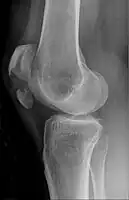

Diagnosis

A vertical patella fracture with the fracture line marked by a black arrow

Diagnosis is based on symptoms and confirmed with X-rays.[3] In children an MRI may be required.[3]